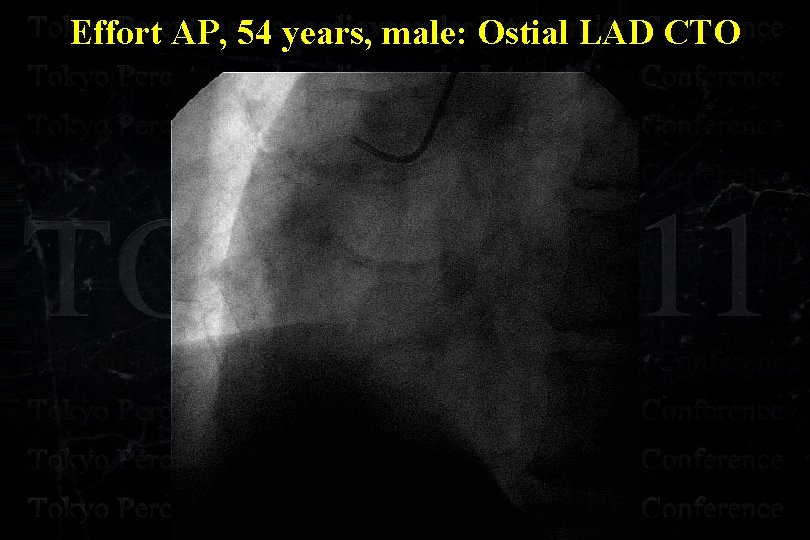

Effort AP, 54 years, male: Ostial LAD CTO

Effort AP, 54 years, male: Ostial LAD CTO

Effort AP, 54 years, male: Ostial LAD CTO

Effort AP, 54 years, male: Ostial LAD CTO

Effort AP, 54 years, male: Ostial LAD CTO

Effort AP, 54 years, male: Ostial LAD CTO

Effort AP, 54 years, male: Ostial LAD CTO Separated Conus Branch !